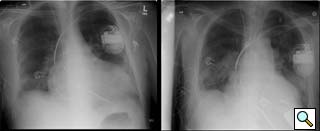

Figure 9: Pre- and postoperative chest radiographs in a 6’7” male demonstrating ventricular decompression.

3. Some will argue that the output of continuous flow pumps like the Jarvik 2000 is inadequate for certain patients. Although intrathoracic placement of the Heartmate pump has been described [9], pump size limits this approach to larger patients. The Jarvik 2000 has provided reliable and sufficient outputs for all of our patients (Figure 9 is a pre and postoperative CXR showing LV decompression in a patient that was 6’7” with a body surface area of nearly 2.3). That said, the Jarvik 2000 is an assist, and not replacement device.